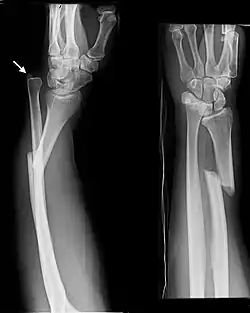

Galeazzi fracture

| Galeazzi fracture. Arrow points at the dislocated ulnar head | |

The Galeazzi fracture is a fracture of the distal third of the radius with dislocation of the distal radioulnar joint. It classically involves an isolated fracture of the junction of the distal third and middle third of the radius with associated subluxation or dislocation of the distal radio-ulnar joint; the injury disrupts the forearm axis joint.[1]

Galeazzi fractures are best treated with open reduction of the radius and the distal radio-ulnar joint.[3] It has been called the "fracture of necessity," because it necessitates open surgical treatment in the adult.[4] Nonsurgical treatment results in persistent or recurrent dislocations of the distal ulna.[1] However, in skeletally immature patients such as children, the fracture is typically treated with closed reduction.[1]